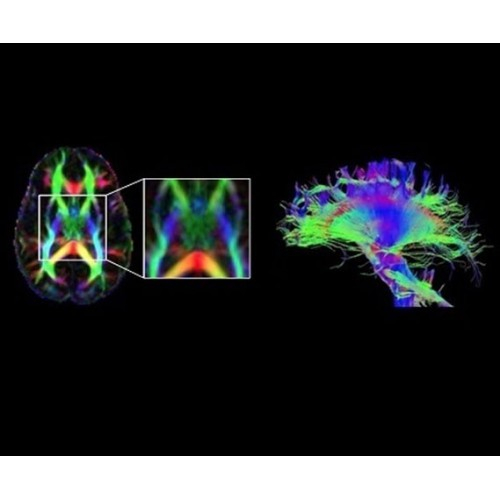

Используйте весь диагностический потенциал TOF

В систему SIGNA PET/MR встроены запатентованные детекторы кремниевого фотоумножителя (SiPM) и сверхчувствительные кристаллические сцинтилляторы на основе лютеция толщиной 25 мм. Благодаря этому обеспечивается исключительная чувствительность и возможность использования времяпролетной диагностики (TOF).

Кроме того, в результате использования технологии TOF и инновационной технологии реконструкции Q.Clear вы сможете добиться прекрасного соотношения сигнал/шум. А благодаря технологии нулевого времени эхо (ZTE) визуализировать костную структуру без ионизирующего излучения. Все эти разработки для улучшения качества сканирования и точности анализа помогут вам использовать весь потенциал ПЭТ/МРТ.

В системе SIGNA PET/MR есть все инструменты, необходимые для выявления маркеров разных заболеваний и для создания новых протоколов. ПЭТ/МРТ можно использовать совместно с мультиядерной спектроскопией в лаборатории in vivo для изучения быстрых биохимических процессов. Кроме того, PET ToolBox и набор инструментов Orchestra предоставляют персональный доступ к функциям реконструкции изображений для ПЭТ и МРТ, ускоряя и упрощая работу с необработанными данными.

• Orchestra — получайте прямой доступ к необработанным данным изображений для редактирования в среде реконструкции с SIGNA PET/MR.

• PET ToolBox — разрабатывайте новые методики ПЭТ с помощью наших программных инструментов для доступа к среде реконструкции ПЭТ-изображений.